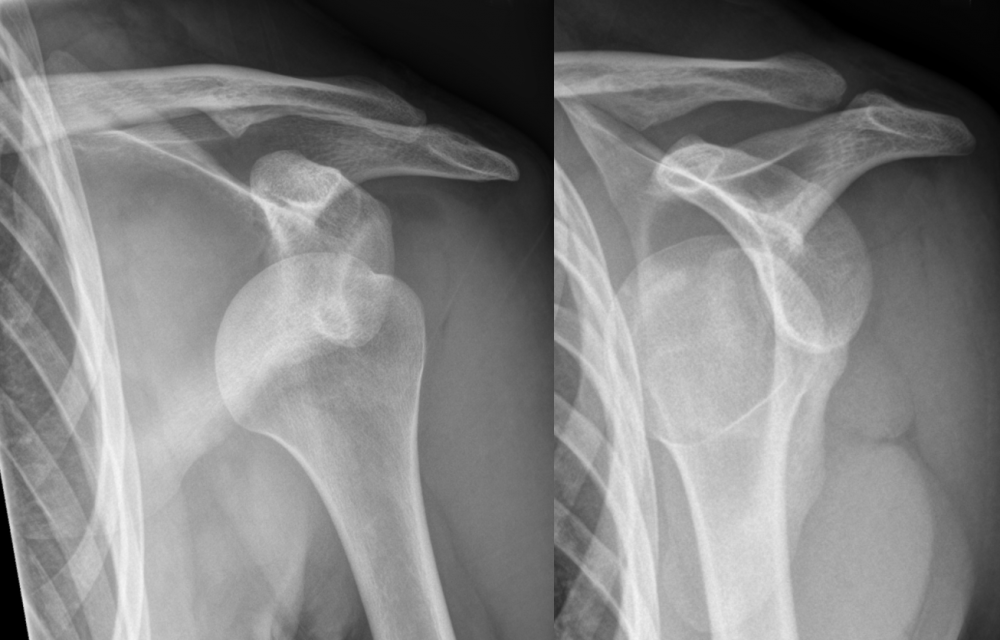

Un dels informes mèdics per rebatre l’actuació a Urgències és clar: “Després d’efectuar el primer intent de reducció, la radiografia mostra un gran desplaçament dels fragments de la fractura. En aquestes condicions, no s’ha d’efectuar un nou intent de reducció, doncs la fractura és inestable, i la seva solució és quirúrgica. A més a més, hi ha un alt risc d’aparició de complicacions”

S’hi afegeix, a més, que “el dia de l’accident es va produir una fractura de glenoides que es podria haver reparat en l’acte quirúrgic ja que juntament amb les lesions musculo-lligamentàries que existeixen a dia d’avui, fan la espatlla molt inestable amb tendència a la subluxació”. Un altre dels informes mèdics sol·licitats per mirar d’aclarir tot plegat indica que “després d’efectuar el primer intent de reducció, la radiografia mostra un gran desplaçament dels fragments de la fractura. En aquestes condicions, no s’ha d’efectuar un nou intent de reducció, doncs la fractura és inestable, i la seva solució és quirúrgica. A més a més, hi ha un alt risc d’aparició de complicacions”.